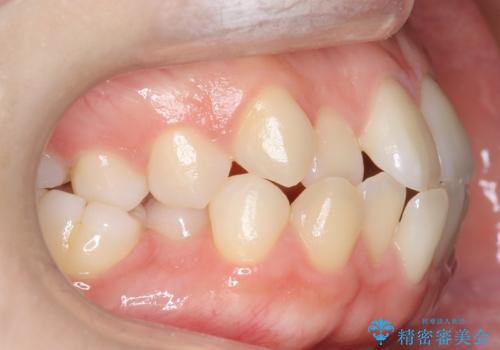

[ マウスピース矯正 ] 長期海外出張中に矯正治療を行いたい